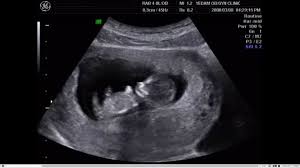

J'ai fait connaissance avec la trisomie, dans une salle d'échographie, un.

Des études à grande échelle réalisées en population générale, donc à plus faible risque de trisomie 21, devront confirmer ce score. Quelles sont ses causes ? Quand faire un test sanguin ? Down syndrome or trisomy 21 is caused by nondisjunction of chromosome 21 in a parent who is chromosomally normal and is one of the most common chromosomal aneuploidy. J'ai fait connaissance avec la trisomie, dans une salle d'échographie, un.